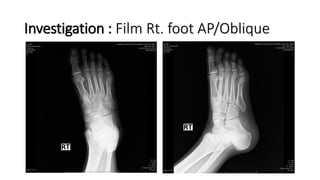

Investigation : Film Rt. foot AP/Oblique

Impression

• Open fracture Rt. 4th-5th metatarsal bone ( Grade II )

Investigation : FilmRt. foot AP/Oblique

• 12.

Impression • Open fractureRt. 4th-5th metatarsal bone ( Grade II )